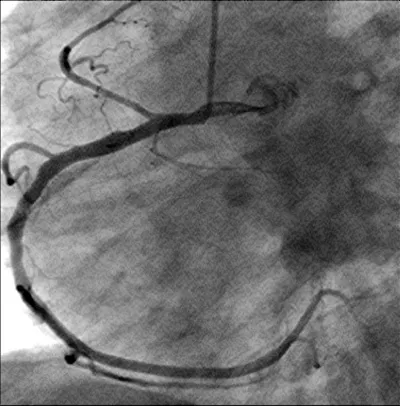

Figure 2: The right coronary artery is shown.

Download Image

Figure 3: The left coronary artery is shown (right anterior oblique projection) with a long dissection of a large ramus circumflexus (RCX).

A 56-year-old obese man with a history of hypertension was admitted at night to the department of cardiology of our hospital because he had developed sudden onset right-sided thoracic pain with radiation into the right shoulder and right arm. He was sweating profusely and had massive nausea. The initially performed 12-lead ECG showed marked inferior ST segment elevations (Figure 1). Beside analgetics and oxygen, he was treated with aspirin, clopidogrel, heparin and the fibrin-specific thrombolytic tenecteplase. His symptoms resolved after 30 minutes. However, half an hour later, he developed left-sided thoracic pain, tachycardia, low blood pressure and the ECG signs of anterior ST-segment elevation myocardial infarction. The performed coronary angiography revealed a normal right coronary artery (Figure 2). The left coronary artery showed a long dissection of a large ramus circumflexus (RCX) (Figures 3,4). Additionally, the left anterior descending coronary artery (LAD) was occluded at about the mid-level (Figure 4, asterisk). Afterwards the left ventriculography revealed a reduced function and a Stanford type A aortic dissection with the intimal flap (Figure 5, arrows). Immediate patient transfer for emergency surgical intervention was arranged. During transport, ventricular fibrillation occurred, and he required endotracheal intubation as well as prolonged cardiopulmonary resuscitation. Unfortunately, he died due to a refractory cardiogenic shock during further transport.